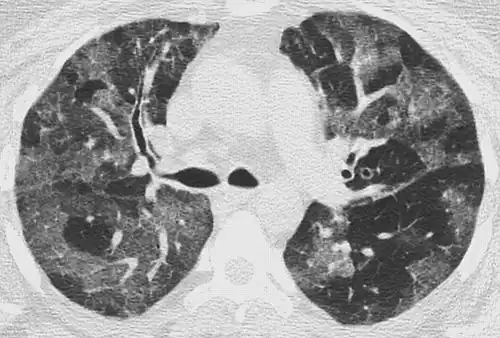

High-resolution CT image showing ground-glass opacities in the periphery of both lungs in a patient with COVID-19 (red arrows). The adjacent normal lung tissue with lower attenuation appears as darker areas.

Ground-glass opacity is among the most common imaging findings in patients with confirmed COVID-19.[16][17] One systematic review found that among patients with COVID-19 and abnormal lung findings on CT, greater than 80% had GGOs, with greater than 50% having mixed GGOs and consolidation.[16] GGOs with mixed consolidation has most often been found in elderly populations.[18]

Several studies have described a pattern among initial, intermediate, and hospital discharge imaging findings in the disease course of COVID-19. Most commonly, initial CT imaging reveals bilateral GGOs at the periphery of the lungs. During initial stages, this is most often found in the lower lobes, although involvement of the upper lobes and right middle lobe has also been reported early in the disease course.[16][18] This is in contrast to the two similar coronaviruses, SARS and MERS, which more commonly involve only one lung on initial imaging.[19][20] As the COVID-19 infection progresses, GGOs typically become more diffuse and often progress to consolidation.[11][18] This is sometimes accompanied by the development of a crazy paving pattern and interlobular septal thickening.[18] In many cases the most severe pulmonary CT abnormalities occurred within 2 weeks after symptoms began.[17] At this point, many individuals begin showing resolution of consolidation and GGOs as symptoms improve. However, some patients have worsening symptoms and imaging findings, with further increase in septal thickening, GGOs, and consolidation. These patients may develop lung "white-out" with progression to acute respiratory distress syndrome (ARDS) requiring treatment escalation.[17][21]